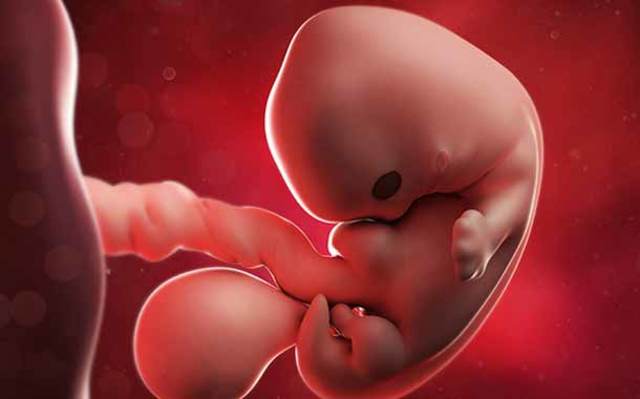

• Semana 6

Semana 6

-Mide 2 cm de largo.

-Los ojos ya están muy separados.

-La cabeza es más grande a comparación del cuerpo.

• Semana 7

Semana 7

-Formación de los parpados.

-El mentón esta poco formado.

-LVC 18 mm.